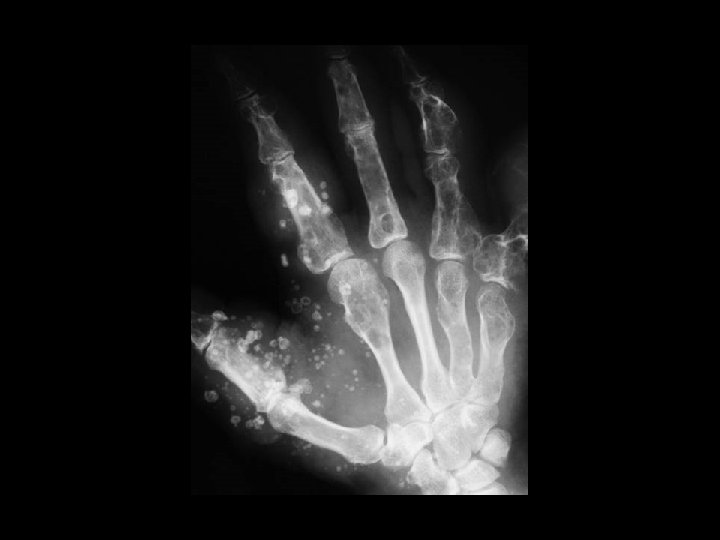

Mafucci syndrome • Findings: – Multiple enchondromas and soft tissue hemangiomas • ddx: – NONE! – This is an Aunt Minnie!

Synovial osteochondromatosis • Findings: – Multiple round calcified masses in the joint space – Erosions on both sides of the joint – Single joint involvement • ddx: – Primary (idiopathic) – Secondary to OA